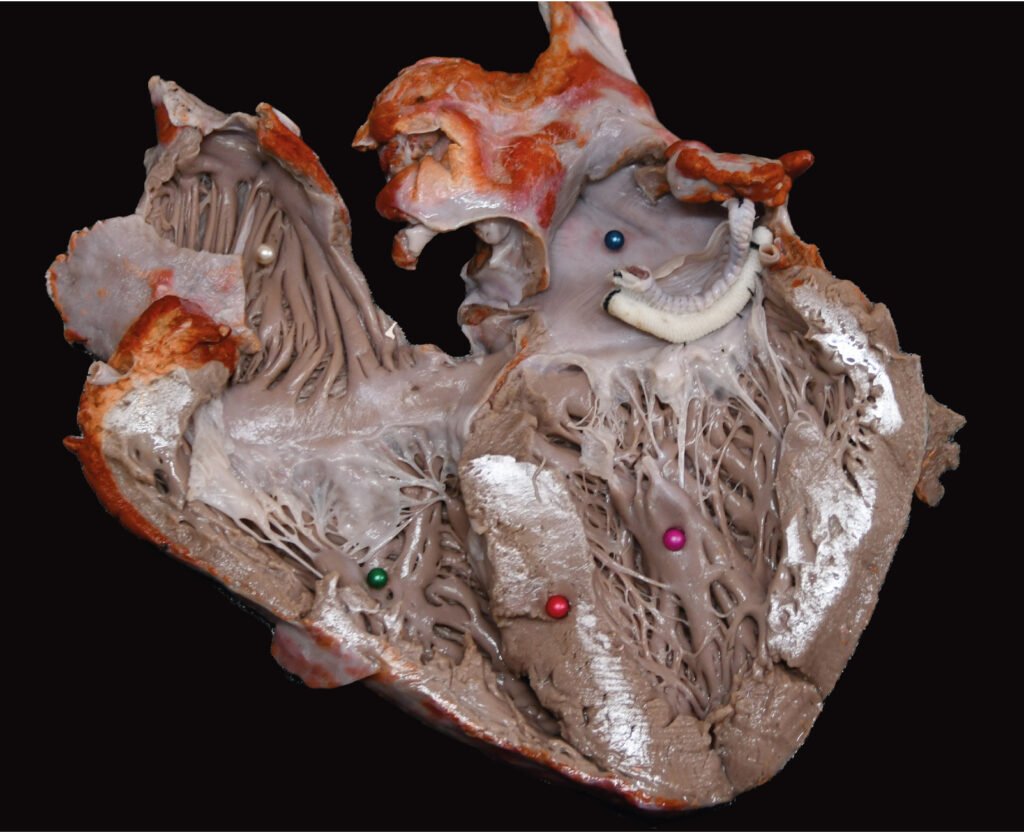

Museo.

Encontrarás los preparados de nuestro laboratorio en el museo de Anatomía J. J. Naón, Facultad de Medicina, Universidad de Buenos Aires, con su descripción.

Encontrarás los preparados de nuestro laboratorio en el museo de Anatomía J. J. Naón, Facultad de Medicina, Universidad de Buenos Aires, con su descripción.